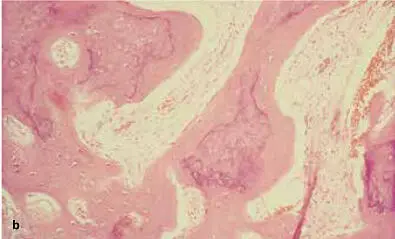

FIG 1-16 (a and b) At about 6 weeks, the graft begins a major resorption-remodeling cycle in which osteoclasts resorb the disorganized immature bone and release BMP and insulinlike growth factors, thus inducing formation of new bone that will mature during function. (Reprinted with permission from Marx and Garg. 1)

FIG 1-18Histomorphometry of an autogenous bone graft without PRP at 4 months shows that the graft has a 60% trabecular bone density, consists mostly of immature bone, and is undergoing active resorption-remodeling. (Reprinted with permission from Marx and Garg. 1)